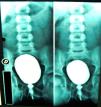

Antecedentes personales: niña sana con control de esfínteres a los dos años de vida. A los 4 años consultó por cuadro de fiebre elevada junto con dolor en flanco derecho. Ante sospecha de pielonefritis aguda (PNA) por Escherichia coli inició tratamiento con una cefalosporina oral de segunda generación resolviéndose el cuadro. A lo largo de los 2 años siguientes presentó 5 nuevos episodios de ITU con urocultivos positivos a infección por E. coli, y fue diagnosticada de sospecha de PNA derecha en el último de ellos. Se prescribió tratamiento profiláctico con cotrimoxazol. Las pruebas de función renal y la ecografía no mostraron datos anómalos. En la cistouretrografía miccional (CUMS) se objetivó un reflujo vesico-ureteral (RVU) derecho grado I (fig. 1).

En la cistografía que aportaba la paciente, además del RVU ya descrito, se objetivaba una vejiga de dimensiones normales pero con paredes de aspecto espiculado y uretra posterior dilatada.